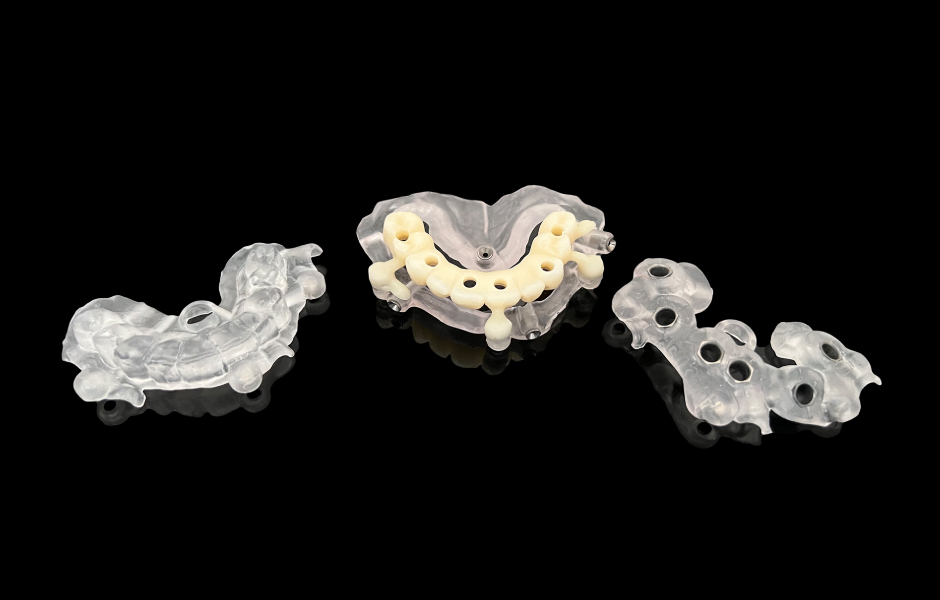

Na základě digitálně získaných informací – od CT vyšetření a registrace skusu až po STL soubor otisku – byla před chirurgickým výkonem navržena a vyrobena modulární chirurgická šablona (Co-DiagnostiX, Dental Wings) a současně i okamžitá provizorní rekonstrukce metodou CAD/CAM.

Obr. 5: Plánované implantáty z hlediska velikosti, délky a orientace.

Obr. 6: Návrh a výroba modulární chirurgické šablony s okluzálně-palatinálními vstupy pro šrouby.

Obr. 7: Návrh a výroba modulární chirurgické šablony s okluzálně-palatinálními vstupy pro šrouby.

Obr. 8: Návrh a výroba modulární chirurgické šablony s okluzálně-palatinálními vstupy pro šrouby.